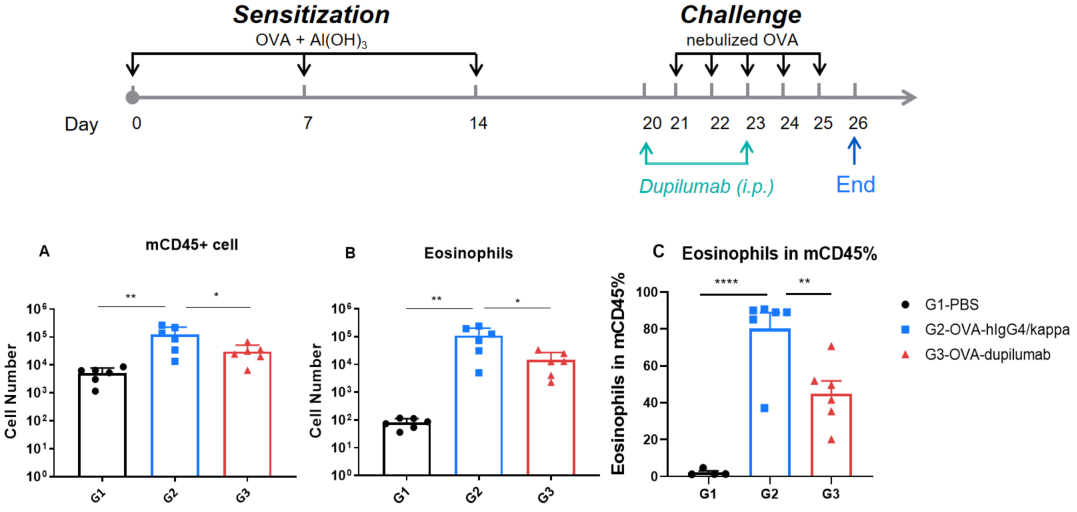

Quantification of immune cells in BALF of OVA-induced B-hIL4/hIL4RA asthmatic mice. Asthma was induced in B-hIL4/hIL4RA mice by OVA sensitization and challenge. (A) CD45⁺ cell count, (B) eosinophil count, and (C) eosinophil proportion among CD45⁺ cells in BALF. G2 (OVA-only) mice showed significantly increased leukocyte infiltration and eosinophil levels compared to G1 controls, indicating successful model induction. Treatment with in-house dupilumab markedly reduced CD45⁺ cell and eosinophil counts relative to the G2 group.